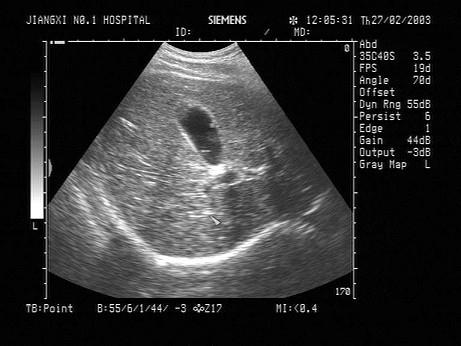

问题 男,37岁,健康体检,偶感上腹不适。声像图如图所示,诊断为?(?)

选项 A.胆囊结石 B.胆囊息肉 C.胆汁淤积 D.胆囊腺瘤 E.胆囊癌

答案 B